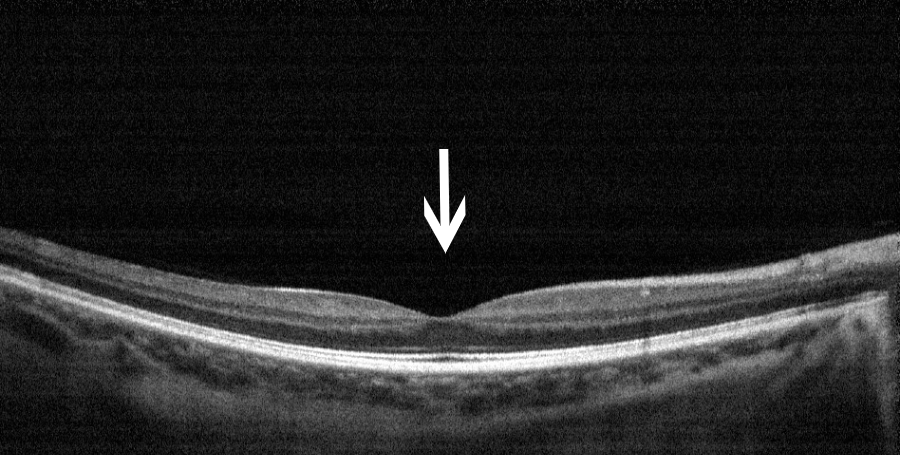

OCT:黄斑区视网膜的断面图,凹陷处为黄斑中心凹

图片来源:天津市眼科医院